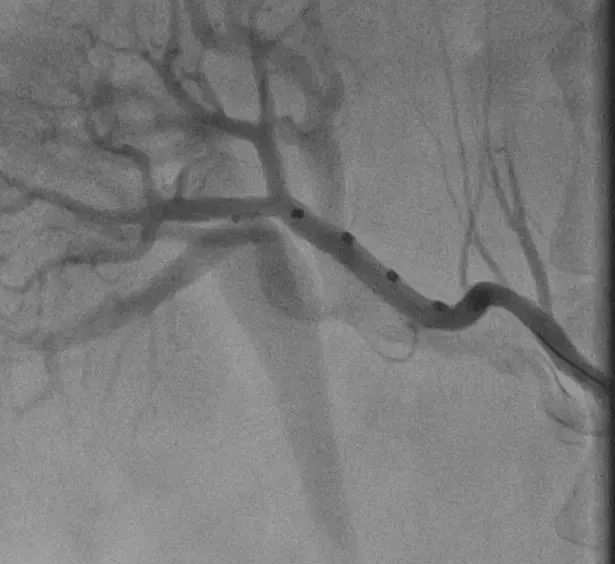

医院积极联系了海南省人民医院王圣教授共同制定手术方案和现场手术指导,心血管介入团队与麻醉科、介入室密切配合,顺利将RDN消融导管送达迂曲的肾动脉分支部位,消融了患者双侧肾动脉主干及分支的77个位点。

术中消融

8月6日,手术团队精密配合,为该病友顺利实施了RDN手术。该病友术中无不良反应,术后复查造影显示肾动脉血流正常,无明显血管损伤。